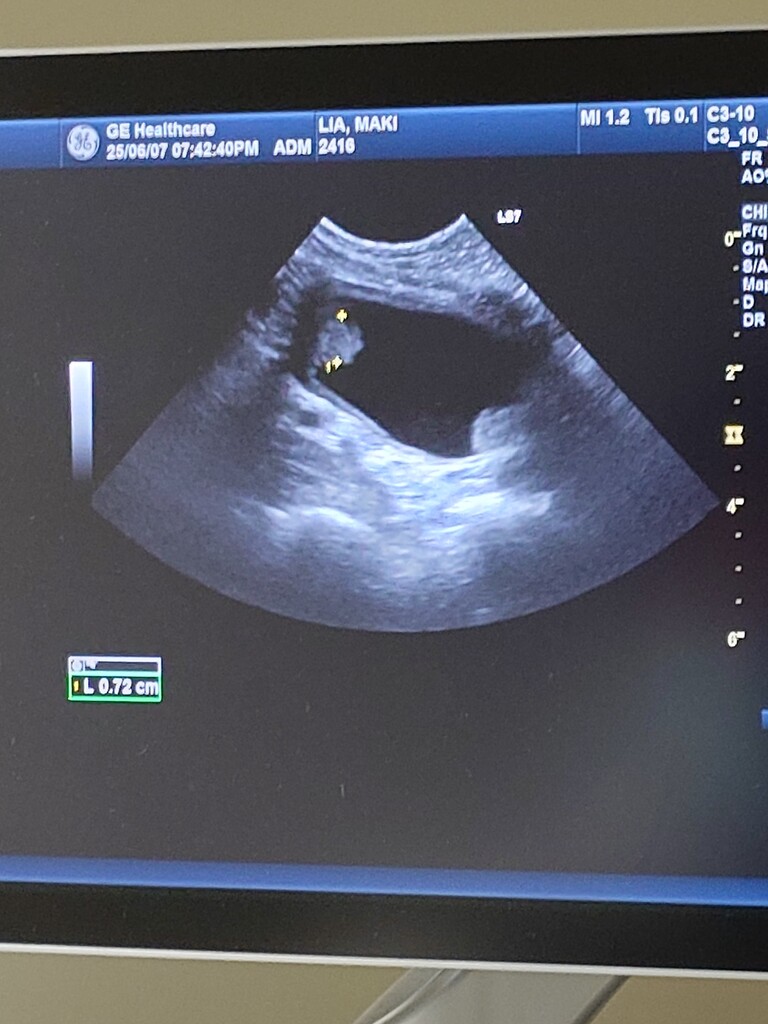

動画を見せたところ

明らかに痛みがあり、かばっているとの事。

癌や皮膚炎で薬を飲んでいる事もあり

3日程服用を止めて見て

20日に院長先生の再診予定です。